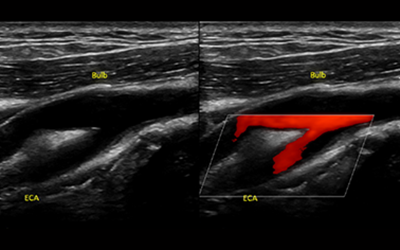

경동맥 초음파 검사는 목 부위에 위치한 경동맥의 상태를 실시간으로 확인할 수 있는 비침습적인 검사 방법입니다. 초음파를 이용하여 혈관 벽의 두께, 혈액의 흐름, 혈관 내 플라크(혈전)의 존재 여부 등을 파악할 수 있습니다. 마치 도로 위에 설치된 CCTV처럼, 혈관 속 상황을 안전하게 들여다보는 것이죠. 검사 과정은 간단하며, 통증이나 불편함이 거의 없어 누구나 부담 없이 받을 수 있습니다.

경동맥 협착은 경동맥 내부에 플라크가 쌓여 혈관이 좁아지는 질환입니다. 혈관이 좁아지면 뇌로 가는 혈류량이 감소하여 뇌졸중의 위험이 증가합니다. 경동맥 초음파 검사를 통해 협착의 정도를 정확하게 파악하고, 필요한 경우 약물 치료나 수술적 치료를 통해 뇌졸중을 예방할 수 있습니다.